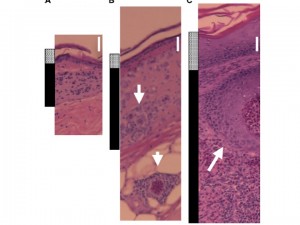

We have ongoing studies in a variety of avian and mammalian systems that are exploring how vertebrate immunological responses affect blood feeding arthropods and pathogen transmission.